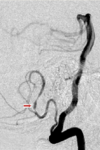

Explain the concept of crossed findings seen in brainstem strokes

Crossed findings = ipsilateral CN findings (b/c CN don’t decussate) and contralateral sensory/motor findigns (corticospinal tract decussates caudally at medullary pyramids)

ex: lesion shown would give ipsilateral 3rd nerve palsy w/ contralateral motor/sensory deficits